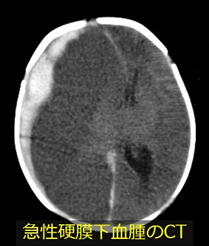

頭部外傷における画像診断法としては頭部CTを行います。ただ、無用な放射線被曝を避けるために、神経症状や嘔吐を伴う場合、高エネルギー外傷が疑われる場合などにのみ実施するのが良いでしょう。当科では,被爆量のきわめて少ないレントゲンを活用して被爆低減に努めています。

代表的な頭蓋内出血には急性硬膜外血腫や急性硬膜下血腫があります。いずれも多量の血腫が脳を圧迫している場合には緊急手術を要します。